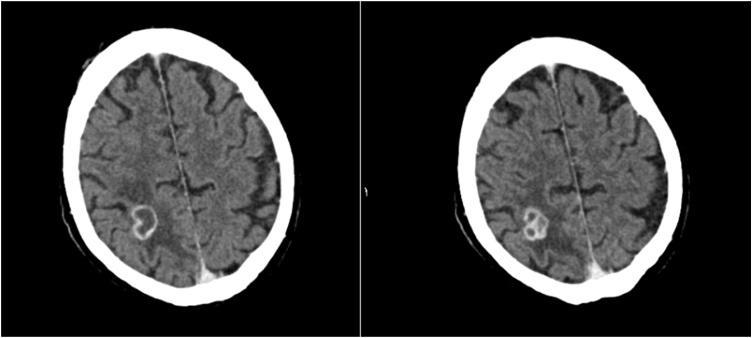

This diagnosis of BA precluded the patient from prompt HTX, which was urgently indicated for the LVAD system infection. With antibiotic therapy of Rifampicin and Ceftriaxone the patient experienced relief of his visual symptoms as well as general condition and clinical presentation improved. Ceftriaxone was administered in dosage of 4 g daily to facilitate Ceftriaxone to pass hemato-encephalic barrier to reach BA. Contrast CCT after one week of treatment in our center showed slightly diminished lesions (19 × 18 × 20 mm) with an additional slight regression of the surrounding edema encouraging us to pursue the antibiotic regime to achieve HTX listing for this patient (Fig. 2).

Fig. 2.

CT Scan with contrast with a 19 × 18 × 20 mm lesion and minimal regression of the surrounding edema.